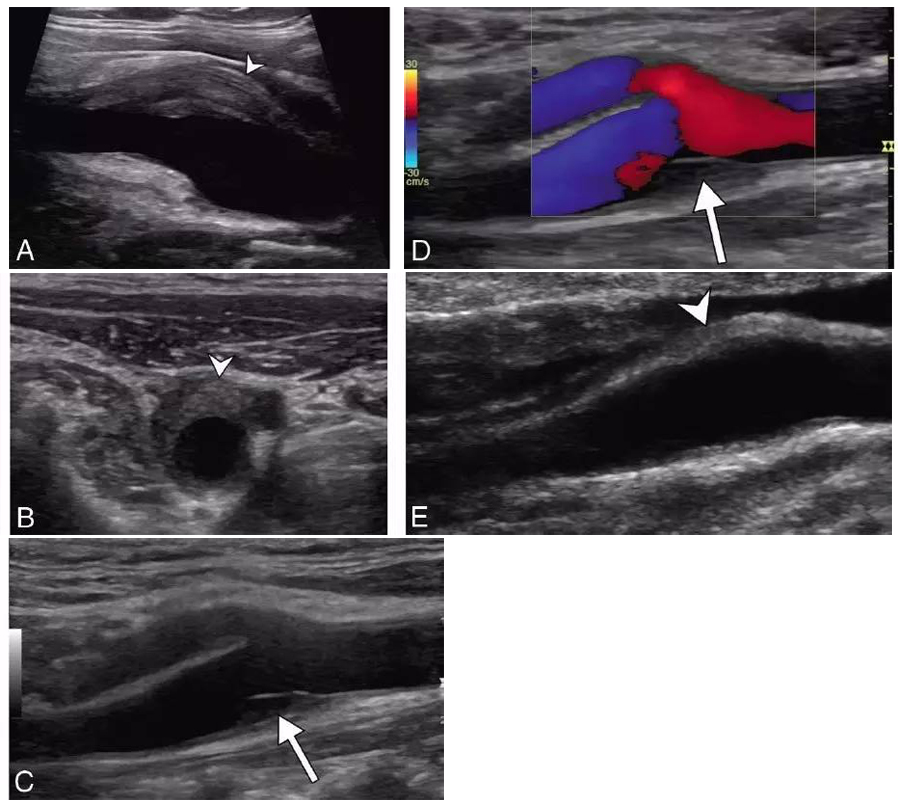

例1:超声(图A-D)显示颈动脉分叉处血管周围偏心浸润(短箭头),伴随内膜斑块(长箭头),管腔轻度狭窄。随访超声(图E)显示血管周围浸润明显减轻(短箭头),内膜斑块完全消失。